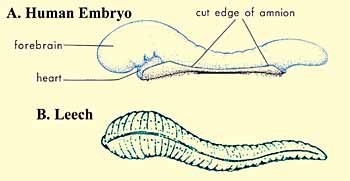

در مرحله علقه، شباهتی بین زالو و جنین [1] پیدا می کنیم که در شکل 1 میبینیم. همچنین جنین در این مرحله مانند زالو که از خون دیگران تغذیه می کند، از خون مادر تغذیه میکند. [2]

شکل 1: این نمودار شباهت های ظاهری بین زالو و جنین انسان در مرحله علقه را نشان میدهد.